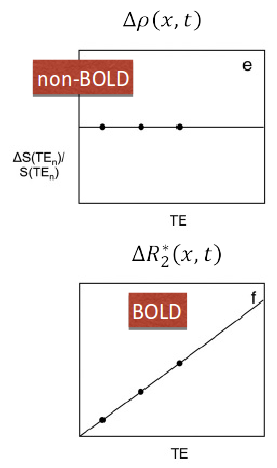

ME-ICA

Assuming monoexponential decay, we can express the

signal percentage change as:

\[ S_{SPC} \approx \Delta\rho - TE \cdot \Delta R_2^{\star} + n \quad where \enspace R_2^{\star} = \frac{1}{T_2^{\star}} \]

This let us differentiate BOLD-related (\(\Delta R_2^{\star}\)) from non-BOLD related (\(\Delta\rho\)) changes

Kundu et al. 2012 (NeuroImage)

If we apply ICA, we can fit the timeseries of the components to either sub-models and automatically classify them